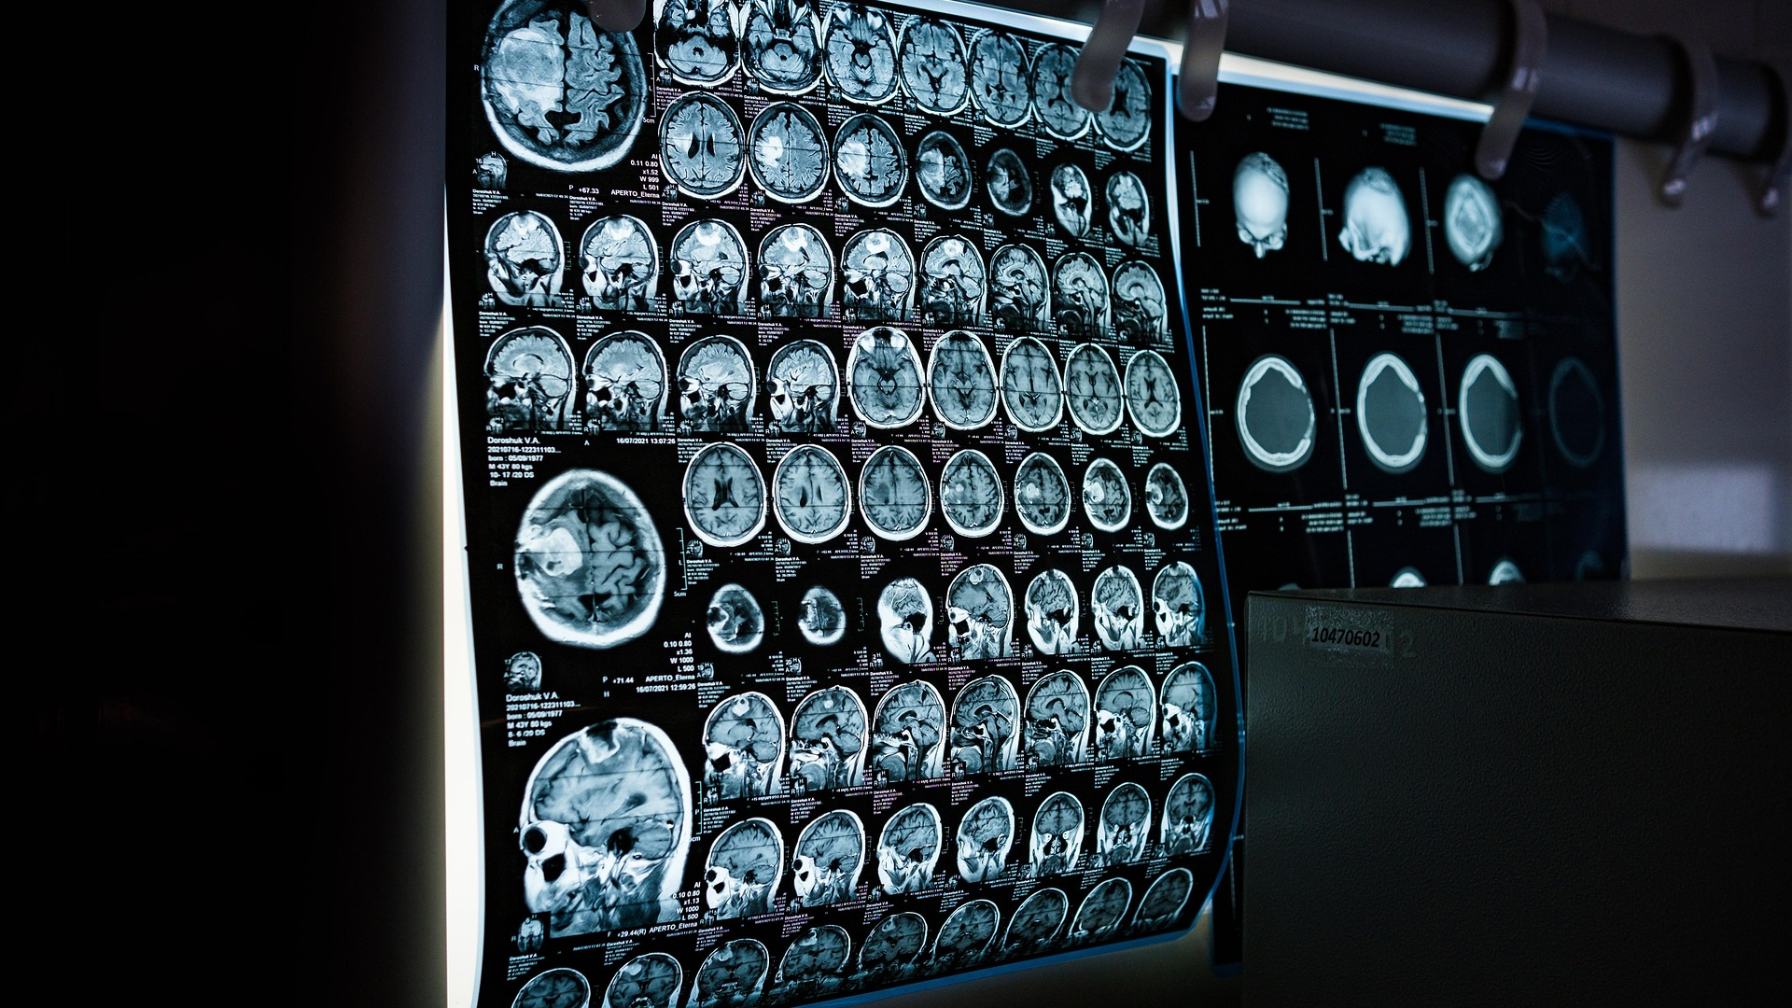

Одним из важных направлений является использование ИИ при диагностике инсульта. Система автоматизированной диагностики Cerebra уже внедрена в 9 инсультных центрах страны.

Технология позволяет оперативно выявлять признаки инсульта на ранних стадиях, что способствует более быстрому принятию клинических решений и своевременному началу лечения. В результате внедрения системы применение тромболитической терапии увеличилось на 40%. В 2026 году планируется масштабирование решения до 33 инсультных центров.

В онкологической службе внедряются решения по ранней диагностике заболеваний, разработанные компанией WDSoft. Использование технологий ИИ при анализе радиологических изображений позволяет выявлять рак молочной железы и лёгких на ранних стадиях.

Благодаря применению ИИ выявляемость онкологических заболеваний увеличилась на 32%, а время диагностики сократилось с 40 до 10 минут. В настоящее время проект реализуется в 190 медицинских организациях 12 регионов страны, и его дальнейшее масштабирование продолжается.